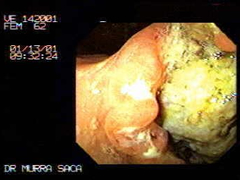

Paciente Femenino de 62 años:

Quien fue tratada por adolecer de anemia por un año sin hacerle ningún estudio, solamente le inyectaban hierro, por vez primera acude a la consulta con historia de haber perdido más de 20 libras y dolor abdominal acompañado de vómitos se le procedió a practicar el estudio de endoscopia detectándosele un intenso carcinoma del antro gástrico. El día de dicho estudio fue unas horas antes del gran terremoto el 13 de Enero 2001.